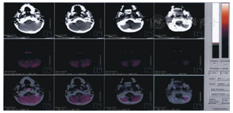

15例患儿中,临床诊断脑瘫(共济失调型)10例(67%),主要临床资料见表3。其中男、女各5例;起病年龄1~10(5.5±4.5)个月;首次住院年龄4个月~3岁6个月,康复治疗疗程3~58个月,康复治疗不足1年者均临床随访至少1年观察病情无进行性恶化以排除遗传代谢性疾病等神经系统进展性疾病;10例患者均在婴儿期起病,首发症状为运动发育落后,肌张力低下,均有下肢共济失调表现,部分伴躯干或/和双上肢受累,9例伴有智能障碍;10例围生期危险因素有母孕早期上呼吸道感染、先兆流产、羊水少、胎儿宫内窘迫、胎膜早破、产程延长、黄疸等;7例头颅CT或MRI提示存在小脑半球萎缩;3例头颅MRI未发现小脑结构异常,其中2例行头颅PET-CT提示存在小脑神经元功能降低(图1、图2)。6例行血、尿代谢分析未见特异性异常。3例行染色体核型分析未见异常。分析10例共济失调型脑瘫患者康复治疗前后粗大运动功能测试量表(GMFM)总分及Gesell发育量表5个能区DQ,提示康复治疗前GMFM总分为44.15±20.41,康复治疗后GMFM总分为56.42±15.65,二者比较差异有统计学意义(t=-3.121,P<0.05);而Gesell发育量表社会适应、大运动、精细运动、语言及个人社交5个能区DQ,治疗前分别为37.47±14.47、35.23±17.23、37.06±11.51、40.69±12.10、40.41±15.79,治疗后分别为39.44±16.29、28.27±14.65、35.96±10.76、40.26±14.20、38.61±11.95,其中治疗后大运动能区DQ较治疗前下降,差异有统计学意义(t=2.75,P<0.05),余功能区治疗前后比较差异均无统计学意义(P均>0.05),见表4。

Brain positron emission tomography and computer tomography of the patient No.10,showing the radioactive ratio of bilateral cerebellar hemispheres to bilateral temporal lobes was about 0.61

共济失调型脑瘫占所有脑瘫类型的5%~10%[2],属慢性非进行性小脑共济失调范畴,并有报道其占据欧洲世界卫生组织地区儿童共济失调患病率的重要构成部分[14]。据估计大约50%共济失调型脑瘫呈常染色体隐性遗传,McHale等[15]对1个有4例共济失调脑瘫患者的家系利用343个荧光标记多态标志物进行全基因组分析提示致病基因定位在9p12-q12。本组10例共济失调型脑瘫患儿围生期危险因素多样,其与该病的相关性尚未明确,虽部分患者曾行染色体核型分析,血、尿代谢分析未见异常,仍不能排除遗传因素所致。日后对于诊断共济失调型脑瘫患者,有条件者可行DNA芯片检测或多重连接探针扩增技术等基因检测手段以进一步寻找遗传证据;确定相关致病基因可能有助于产前诊断或婚前检查的开展,并可提高对该病的认识。10例中7例头颅MRI或CT提示存在小脑发育不良或小脑萎缩,其中2例在婴儿早期影像学表现不明显,后期复查提示小脑萎缩,患者临床病情相对静止,运动功能缓慢进步,无明显倒退表现;3例患者头颅MRI无明显小脑结构异常,其中2例行头颅PET-CT提示存在小脑神经元代谢功能降低。因此,考虑慢性非进行性小脑共济失调患者多有小脑结构或功能异常,但早期影像学表现可能不明显,临床工作中应注意根据患儿病情定期复查头颅神经影像学检查以明确诊断;且在高度怀疑小脑病变时,即使头颅MRI无阳性发现,可进一步行头颅PET-CT检查以了解小脑神经元代谢功能情况。PET-CT在神经系统疾病的应用日益广泛,大脑皮质中细微的糖代谢、血流等变化可在屏幕上出现不同的图像,凡代谢率高的组织或病变,在PET-CT上呈现明亮的高代谢亮信号,凡代谢率低的组织或病变在PET-CT上呈现出低代谢暗信号[16]。